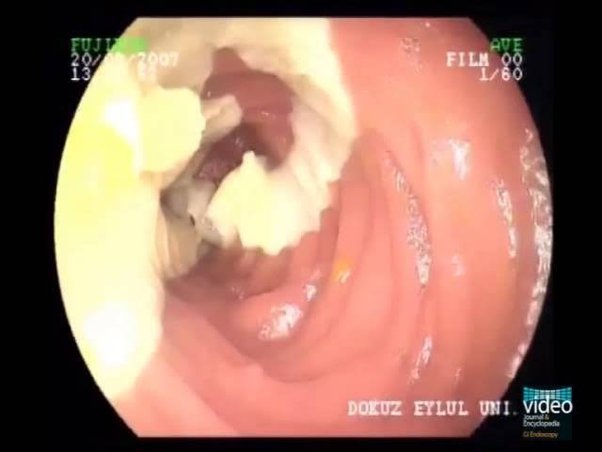

Los parásitos provocan necrosis tisular, que prácticamente conduce a la amputación:

El parásito se alimenta de nuestros tejidos blandos:

Un pulmón destruido desde el interior por parásitos: